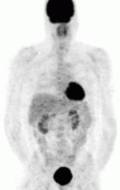

MIBG Scintigraphy — the pheochromocytoma is appreciated in the left panel on the right side of the screen (right panel; left side of the screen) as the darkened circle towards the abdomen. The darkened structure at the head of the patient is the thyroid gland, while the darkened structure in the pelvis of the patient is the bladder. This is normal physiologic uptake.

The first functional imaging technique utilized in pheochromocytoma patients was 123I-MIBG scintigraphy. Given the compound's similar structure to the catecholamine norepinephrine (secreted by pheochromocytomas), MIBG was well-suited for uptake by most neuroendocrine tumors.[94] Furthermore, if a patient was found to be positive on an MIBG scan, they were eligible for MIBG treatment, offering additional avenues for those with widespread metastatic disease.[95] However, further investigation revealed that while MIBG excelled with adrenal lesions, it was far less superior in patients with extra-adrenal paragangliomas, particularly with specific genetic variants like those in the succinate dehydrogenase subunit–encoding genes (SDHx).[83] As the positron emission tomography scans were developed, MIBG has slowly lost its favor for the pheochromocytoma patient.[83]

FDG PET — the tumor is appreciated as the dark structure in the patient's left chest. The darkened structure at the head of the patient is the brain, posterior to the abdomen are the kidneys, and in the pelvis is the bladder. These are normal.

Of the four above mentioned modalities, 18F-FDG PET is the most common and readily available functional imaging technique at most hospital systems, but the least-specific to neuroendocrine tumors (Image Left). In 2012, over 200 patients participated in a trial that compared the current gold standard of the time (MIBG/CT/MRI) to the novel FDG PET. Compared to its functional counterpart, FDG outperformed MIBG in detecting soft-tissue and bone metastases with higher specificity in patients with biochemically active tumors.[83]